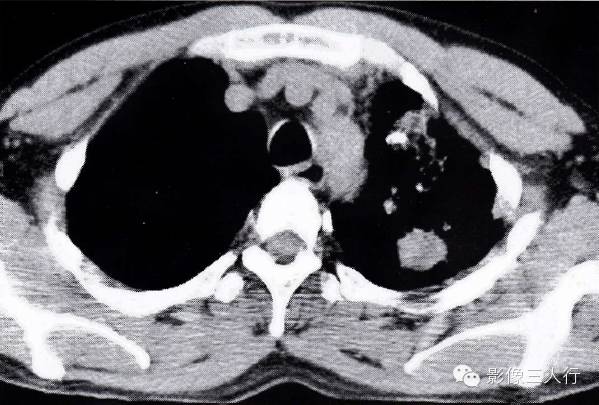

图2-91 肺结核合并肺癌

左肺上叶见多发小斑状影,密度不均,边缘模糊。其内有一结节影,箭头所指。肺穿刺为肺腺癌。肺癌在肺结核的病灶内

肺结核合并肺癌的CT表现及鉴别诊断

图2-92肺结核合并肺癌

与图2-91为同一患者的纵隔窗 左肺上叶结节影,周围还有小斑片状影,其内有小点状钙化影